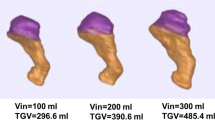

The assessment of the changes induced by bariatric surgery focused on gastric volumetric reduction, gastric mechanical response of the stomach after a simulated inflation (pressure–volume curve), and the distribution of elongation strain at different levels of intragastric pressure. Hence, to simulate an inflation process and thus characterize the total deformation of the gastric walls mimicking the process of food ingestion, a fluid cavity interaction was defined in the internal region of the stomach, while gastroesophageal and gastroduodenal junctions were fixed by imposing null displacement to the upper and lower extremities of the stomach cavity. Each computational analysis was performed by progressively increasing the intracavity pressure up to 40 mmHg during a step time of 1 s. The simulations lasted between 12 and 24 h, running contemporary on 45 threads of a High-Performance Computing Server Fujitsu Primergy RX4770 equipped with two Intel Xeon E7 8890 v4 processors, 256 GB RAM and SSD HD.

Figure 2a shows the extracted patient-specific stomach models (from patient #1 to #23, pre- and post-surgery), and in Fig. 2b the pressure–volume response of each model from 0 to 40 mmHg has been extracted from the computational simulations. The solid lines describe the pre-surgical stomachs during the inflation process, while the dashed lines account for the sleeved stomachs. These latter display a smaller variability, to be expected after LSG, due to the final reduced stomach volume, approximatively the same in all the patients at least in the short term. In particular, as reported in [22], a calibration tube of 32 Fr bougie size was used. In addition, the statistical bands (C.I. 75%) and the corresponding median curves of pre-surgical stomachs and sleeved stomachs are shown in Fig. 3. The computational outputs in terms of volumetric capacity were firstly compared with experimental volumes, to validate the feasibility of the 3D finite element model generation procedure, highlighting no significant differences between the two groups (p = 0.14). Then, experimental volumes and related intragastric pressures obtained through manometry in [22] were plotted with respect to the computational predictions. In Fig. 3, orange circles and blue circles represent pre- and post-surgical measurements, respectively.

Table 3 reports the collection of the computational volumetric capacity of each patient at baseline, i.e., at zero intragastric pressure, which identifies the dimension of empty stomachs, and the reached volume at an inner intragastric pressure of 30 mmHg, which represents a realistic physiological pressure occurring during a meal.

From the extracted geometries reported in Fig. 2a and the simulated volume–pressure curves displayed in Fig. 2b, it emerges that patient-specific stomach models present a wide inter-sample variability both in shape, size, and mechanical behavior, especially in pre-surgical stomachs. This variability displays a typical feature of biological tissues and structures, more evident in pre-surgical curves, which occupied the rightmost part of the chart (related to higher volumes) with respect to the post-surgical settings [22]. These latter models exhibit a more contained variability, because of the volumetric standardization by the calibration tube (in this study 32 Fr bougie size) used for LSG, which forced the patient-specific stomach geometry to a predefined volume, with small oscillations within six months after the surgery. Indeed, statistical analysis clearly shows significant difference between pre- and post-surgical baseline volumes, also when a physiological intragastric pressure of 30 mmHg was applied. Moreover, it was possible to validate the models, when comparing experimental evidences with computational predictions, as reported in Fig. 3. In particular, computational results of post-surgical stomachs showed a good agreement with respect to experimental measurements of intragastric pressure and related volumetric capacity, while for pre-surgical models, they appeared to overestimate the gastric volumes at the same pressure, with respect to the real ones. The main reasons could be related to the adoption of simplified constant pressure, normal to each point of the internal surface (instead of different intragastric pressure levels), to model the ingestion process, and also the lack of the conformational effect of adjacent organs combined with positive intra-abdominal pressure. The first approximation may force the fundus to a hyper-physiological extension, while the second simplification affects the final volume, which resulted greater with respect to the measured one at the same intragastric pressure.